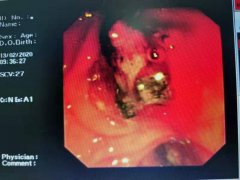

我院消化科:抗疫前线喜讯不断,后方科室同创佳绩